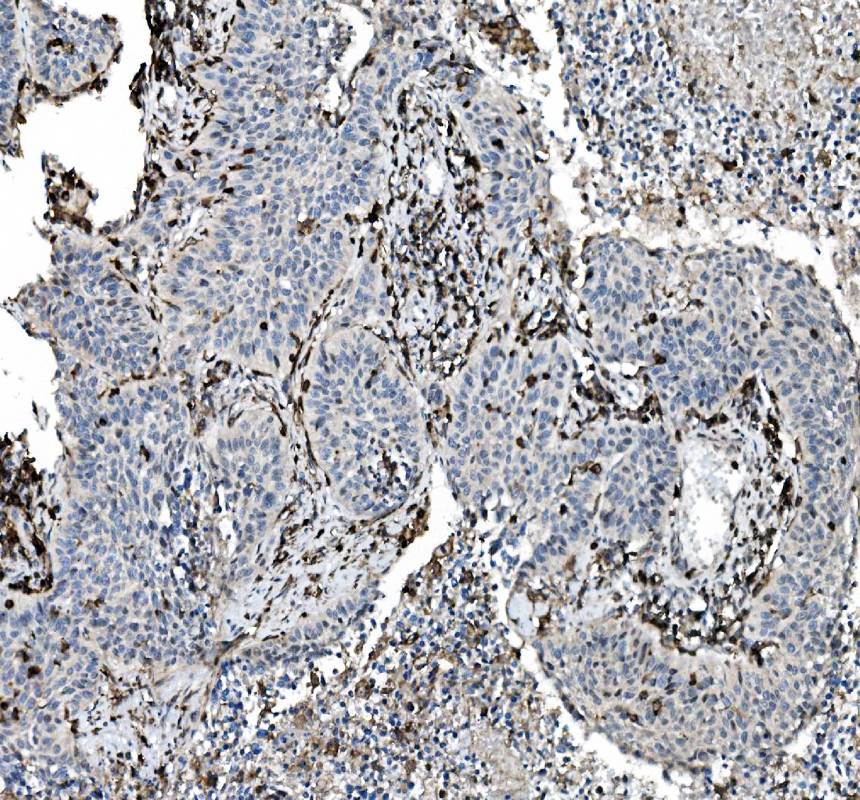

IHC analysis of CD45/PTPRC using anti-CD45/PTPRC antibody (M00555-5).

CD45/PTPRC was detected in a paraffin-embedded section of human lung cancer tissue. The tissue section was incubated with mouse anti-CD45/PTPRC Antibody (M00555-5) at a dilution of 1:200 and developed using HRP Conjugated mouse IgG Super Vision Assay Kit (Catalog # SV0001) with DAB (Catalog # AR1027) as the chromogen.